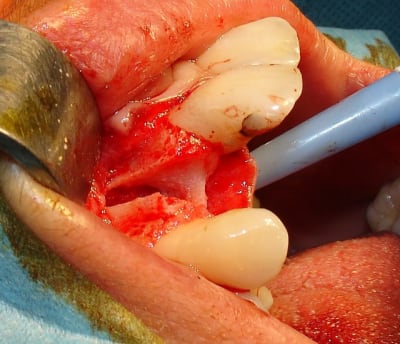

Tiens pour agrémenter! Cet Après midi une extraction implantation. Je n'ai pas oser la mise en charge immédiate si certains l'aurait fait lachez vous.

J'ai fait sauter la table vestibulaire exprès car je ne vois pas comment elle aurait pu etre vascularisée et à part me faire un séquestre osseux et des ennuis j'ai reconstruis.

Regardez les images;

Si certains n'auraient pas extrait argumentez pour traiter en palatin et la felure englobé par le granulome m^me si ce n'est pas mis en évidence sur le scan.

En plus vous voyez le nouvel implant Leone et son indication majeure, c'est vrai que sa mise en place est super aisée, surtout comme celà en palatin.

Os allogénique Tbf + Prf après rinçage abondant au métronidazole. Recouvert d'une membrane Jason Pericardum.

Pour les tissus moux Jason fleece enrobé de 2 Mbnes de Prf; soit pour le "bouchon" 2 épaisseur de prf en dessous et au dessus de la Jason fleece.

Voilà pour le cocktail mon Céramik; je reproduis depuis 5 ans avec assez de réussite.